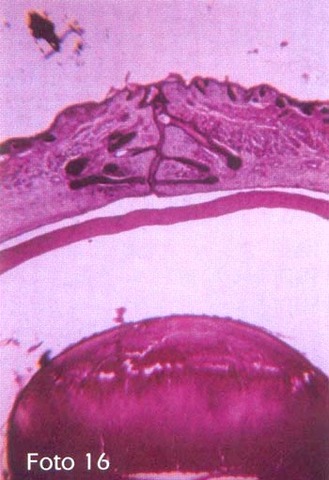

• 5 meses

5 meses

Se aprecia la formación de las glándulas de Meibomio y otras estructuras anexas

Ya se puede apreciar la membrana de Bowman